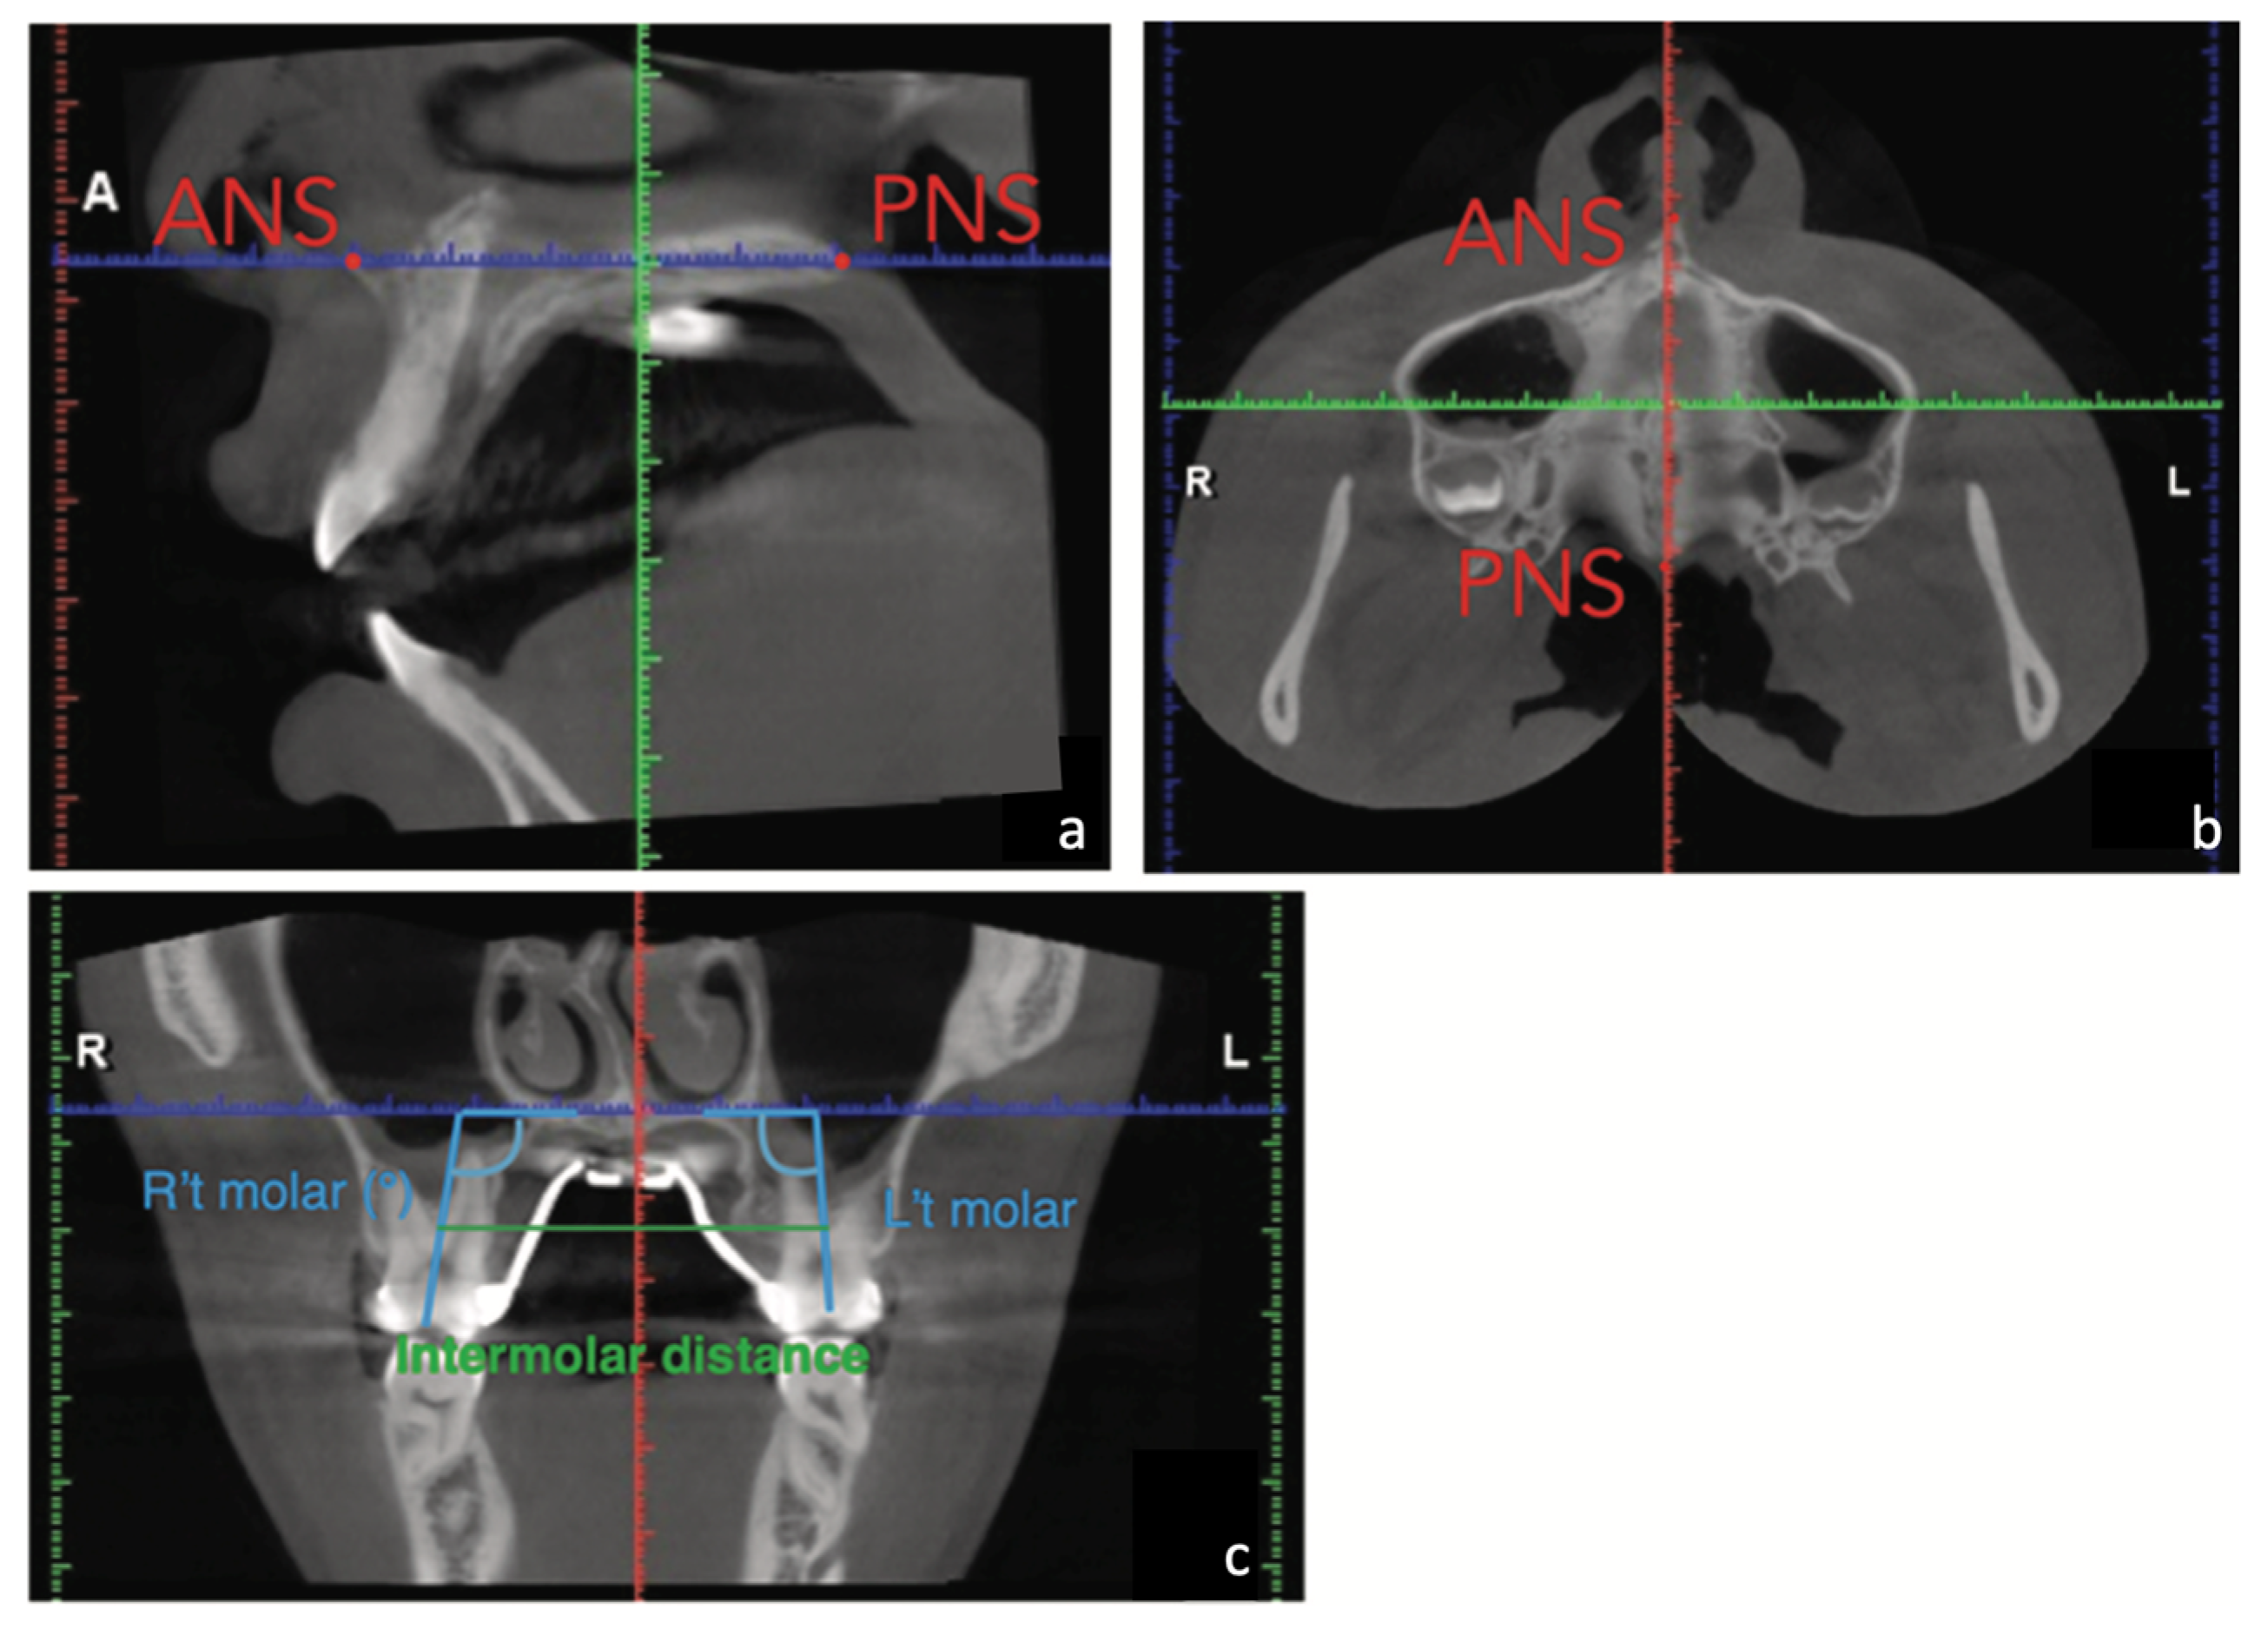

2. Case Report

2.1. Diagnosis and Aetiology